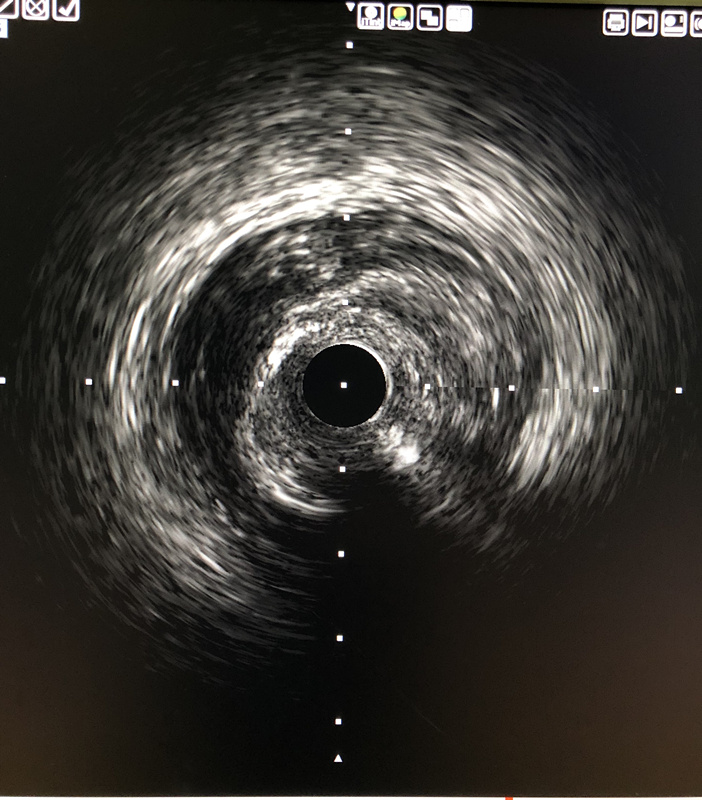

IVUS影像提示导丝位于闭塞段斑块内,斑块以纤维斑块为主。